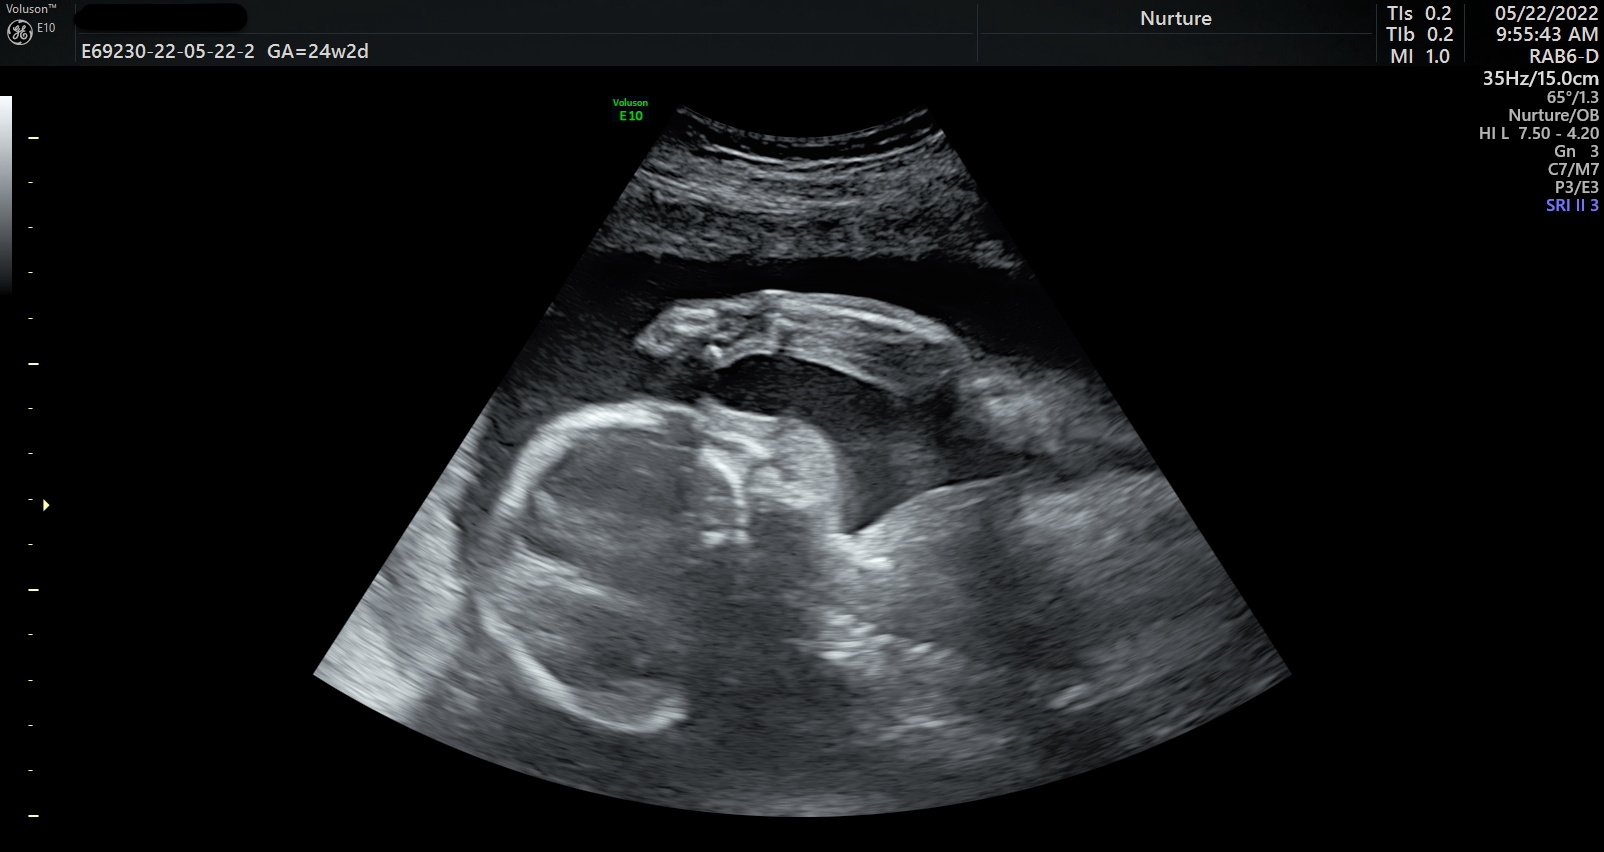

Seeing your baby suck their thumb, purse their little lips together, rub their eyes, and kick their little feet is magical.

Ultrasound image of a fetus inside the womb.

During your session, you’ll watch your baby in real time—seeing their movements, their expressions, their unique rhythms. These are moments of life in utero that are usually unseen, yet deeply felt. Many families describe it as the first time everything becomes real in a new way.

• 2D & 3D are still images, while 4D/HD adds the dimension of motion, so it looks like a video. HD is the newest fetal keepsake ultrasound technology on the market. HD allows you to see all the details of the baby by using software technology to change the focal points and "lighting" of the ultrasound.